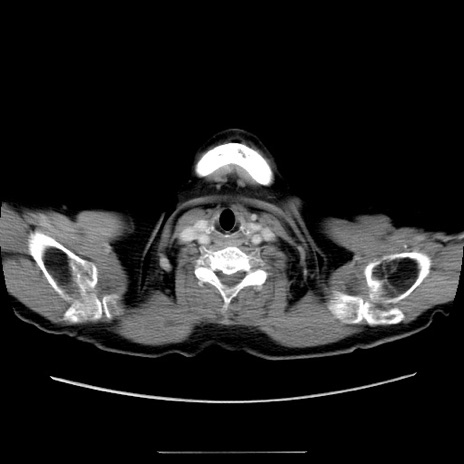

【症例】70歳代女性

【主訴】お腹が張る

【現病歴】1週間くらい前から腹部膨満の自覚あり。昨日夜から増悪したため、本日救急外来受診。

【身体所見】意識清明、BT 36.5℃、BP 165/106mmHg、HR 80bpm、SpO2 98%、腹部:膨満、軟、自発痛・圧痛なし、触診にて不快感あり、腸蠕動音:減弱

【データ】WBC 12600、CRP 1.04